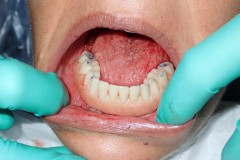

This patient experienced many areas of gum recession, primarily on the upper and lower front teeth. This patient's own tissue was used to correct the problem.